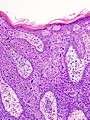

Bowen's disease is essentially equivalent to squamous cell carcinoma in situ. Atypical squamous cells proliferate through the whole thickness of the epidermis. The entire tumor is confined to the epidermis and does not invade into the dermis. The cells in Bowen's are often highly atypical under the microscope, and may in fact look more unusual than the cells of some invasive squamous cell carcinomas.

Bowen's disease as seen under a microscope